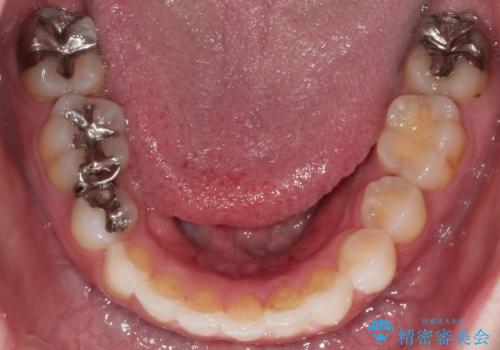

前歯のガタつきを改善 抜歯矯正後の後戻り

- 抜歯矯正後の後戻りで前歯ガタつきが主訴で来院された患者様です。

後戻り矯正や非抜歯矯正はインビザラインをご案内する事が多いですが、自己管理の煩わしさから、目立たないワイヤー装置にて矯正治療を行うこととしました。

後戻りの程度としては軽度なので、治療期間としては短く終えることが出来ました。

前歯の正中線も改善され大変満足して頂きました。